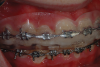

(9.) A thermoplastic tray made directly in the mouth over orthodontic braces facilitates caries control and places the 10% carbamide peroxide into the braces to chemically and mechanically clean them.

Figure 9

(10.) Removal of the tray demonstrates how well the bleaching material penetrates the brackets and arch wires.

Figure 10